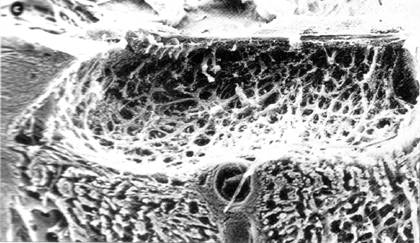

papila nervului optic prezinta excavatie totala, care intereseaza toata suprafata papilara, cu raport C/D = 0.9-1 (Fig.14.9) ; de asemenea papila este decolorata, prezentand atrofie optica.

acuitatea vizuala scade brusc, ireversibil, ducand la cecitate.

Fig. 13.9 - Aspectul histologic al papilei optice in stadiul III de glaucom